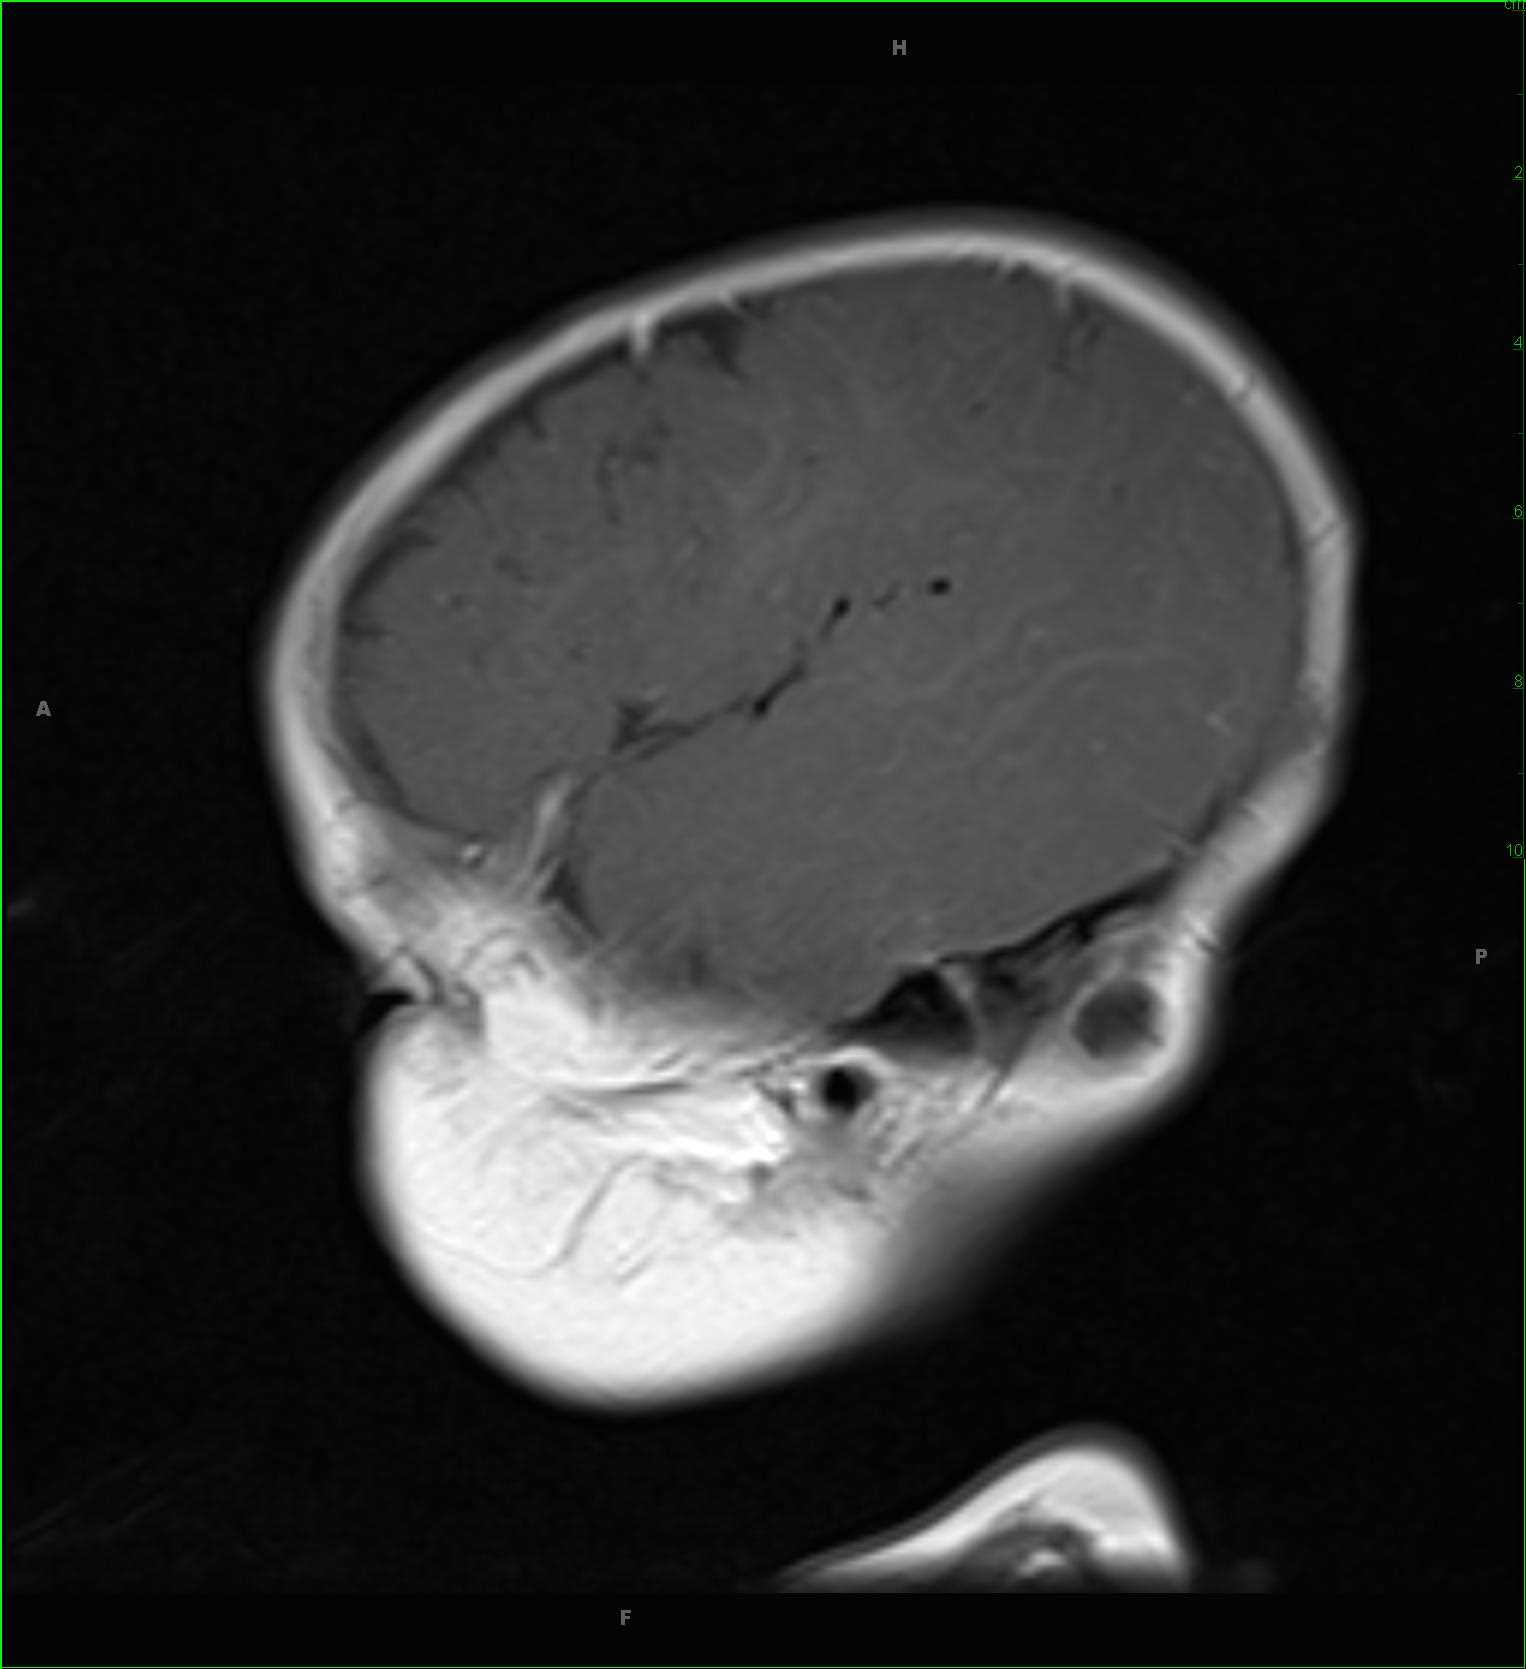

Sinonasal Undifferentiated Carcinoma (SNUC)

63-year-old female with a longstanding history of anosmia and nasal obstruction. There is a T1-hypointense, T2/FLAIR-isointense, enhancing nasal cavity mass. The lesion restricts diffusion. The mass extends into the anterior cranial fossa, including involvement of the olfactory fossa. A differential of esthesioneuroblastoma, squamous cell carcinoma, and sinonasal undifferentiated carcinoma was given. There are T1-hyperintensities in the bilateral maxillary antra and ethmoid air cells compatible with retained secretions and debris secondary to obstruction of the sinus outflow tracts. On biopsy, this mass was a sinonasal undifferentiated carcinoma or SNUC. SNUC is a rare and highly aggressive neoplasm of the paranasal sinuses. Tumors tend to be large and advanced at initial presentation. Prognosis is poor, with treatment typically entailing wide excision followed by radiation and chemotherapy.